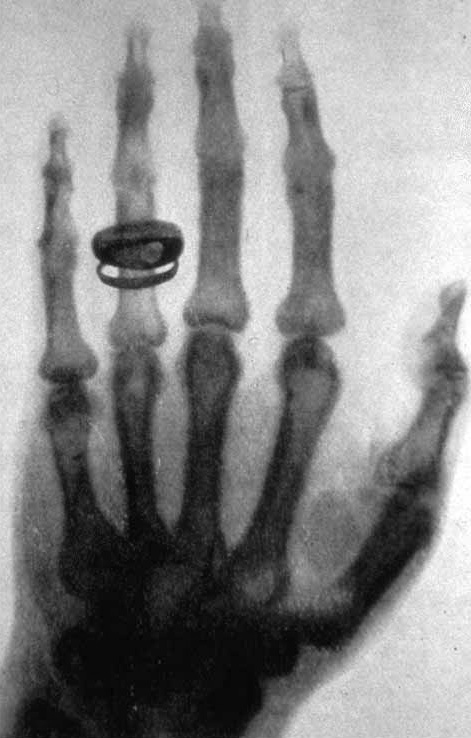

A few weeks later, Röntgen took the first X-ray picture of a human body. It showed the bones inside his wife's hand, along with her wedding ring. When she saw the image, she said, "I have seen my death." People had never looked inside a living body before.

X-rays work because different materials block them by different amounts. Soft things like skin and muscle let most X-rays pass through. Hard things like bone and metal block them. When an X-ray machine shoots rays at your arm and a detector catches them on the other side, bones show up as bright white shapes and soft tissue looks gray. A broken bone shows up as a clear crack in the white.